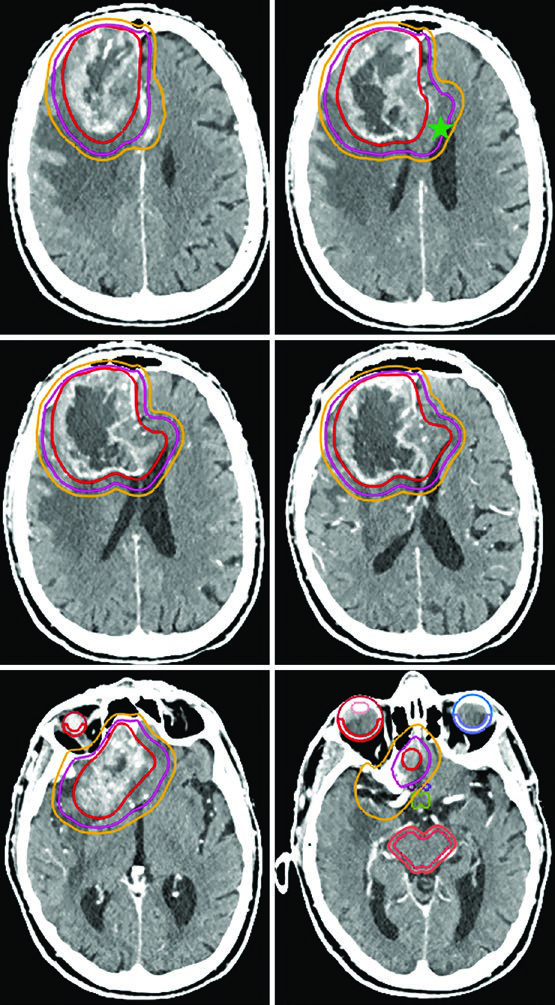

| Glioblastoma | Cone-down: PTV1 46 Gy (2 Gy/fx), PTV2 60 Gy (2 Gy/fx); or SIB: PTV1 50–51 Gy (1.67–1.7 Gy/fx), PTV2 60 Gy (2 Gy/fx) | GTV1: T2/FLAIR volume; GTV2: post-op cavity + residual on post-contrast T1 | CTV1: 2 cm constrained; CTV2: 2 cm constrained | 0.3–0.5 cm |

A critical practical point: anatomically constrained expansions mean the CTV does not cross midline, extend into the pre-pontine cistern, invade the skull, or pass through the tentorium into the posterior fossa. However, tracts at risk for contralateral tumor spread — such as the genu of the corpus callosum — must be explicitly included. This distinction is especially relevant in frontal glioblastomas approaching the callosal fibers.

For the most aggressive prognostic scenarios, ultra-hypofractionated delivery — 25 Gy in 5 fractions (or 30 Gy in 5 fractions as in the illustrated case) — uses 0.5 cm GTV-to-CTV margins. A posterior fossa glioblastoma exemplifies this approach, where the cochlea and brainstem are clearly visible as reference structures for dose optimization.

Gliosarcoma follows the same paradigm as glioblastoma. Two sequential volumes are typically used — the first based on FLAIR (46 Gy) and the second on post-contrast T1 (60 Gy), with 1.5 cm anatomically constrained CTV expansions.